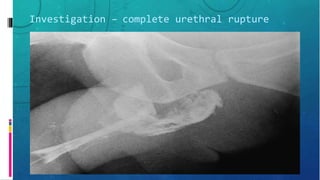

Investigation – complete urethral rupture

– Retrograde urethrography

• Confirms injury

• Location

• Severity

• Presence of foreign body

• Assoc injury e.g. Bladder